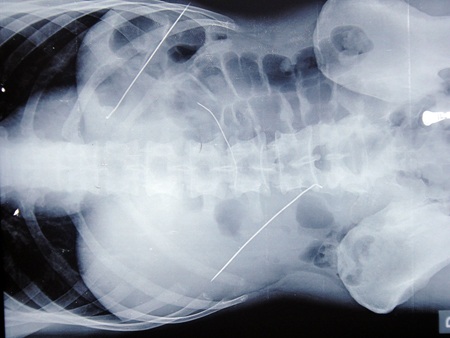

Trước đó, vào ngày 14/8 Bệnh viện Đa khoa tỉnh Hà Tĩnh tiếp nhận bệnh nhân Lê Anh Duẩn, SN 1985, trú tại xã Hương Trạch, huyện Hương Khê trong tình trạng đau bụng dữ dội. Sau khi cho chụp X.Q, phát hiện 3 vật lạ bằng kinh loại dài trong ổ bụng, bệnh viện đã hội chẩn toàn viện đưa ra quyết định mổ ngay để cứu bệnh nhân.

3 thanh kim loại trong ổ bụng bệnh nhân Duẫn lúc chưa mổ

Sau gần 1 tiếng đồng hồ tiến hành mổ, kíp mổ đã lấy được 3 thanh kim loại - là nan bảo vệ cánh quạt điện - trong bụng bệnh nhân, trong đó thanh dài nhất 12cm, thanh ngắn nhất 8cm.